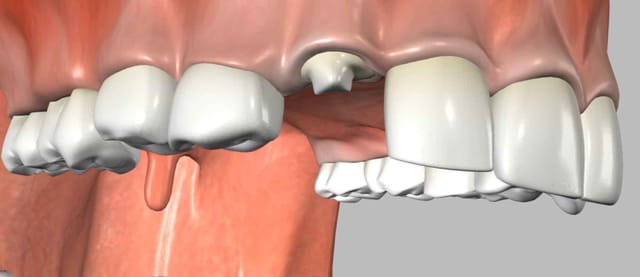

Advanced periodontal disease results in the loss of supporting bone that surrounds the teeth. Bone regeneration may be necessary using the patient's own bone or various bone substitutes.

When a tooth is extracted and an implant is to be placed (either simultaneously or in the future) it is always necessary to complete bone grafting within the residual sockets that are left behind after the roots of the tooth are removed.